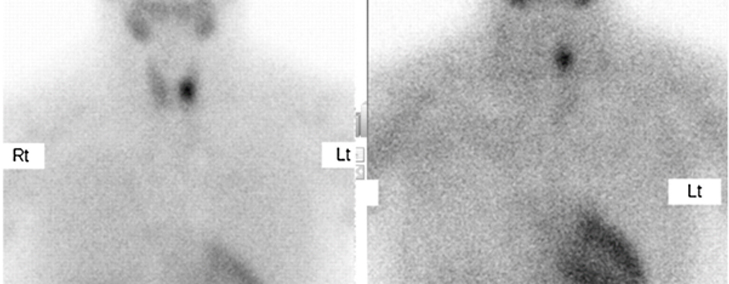

Various methodologies for a Parathyroid Scan are present. The most commonly done method involves injection of a radiotracer known as 99mTc-Sestamibi into the patient intravenously. Then the patient is put under a gamma camera scanner and is imaged two times (once at 10-20 minutes after injection and 1-2 hours after injection). In addition, a thyroid scan and SPECT-CT scan may also be done to improve scan findings.